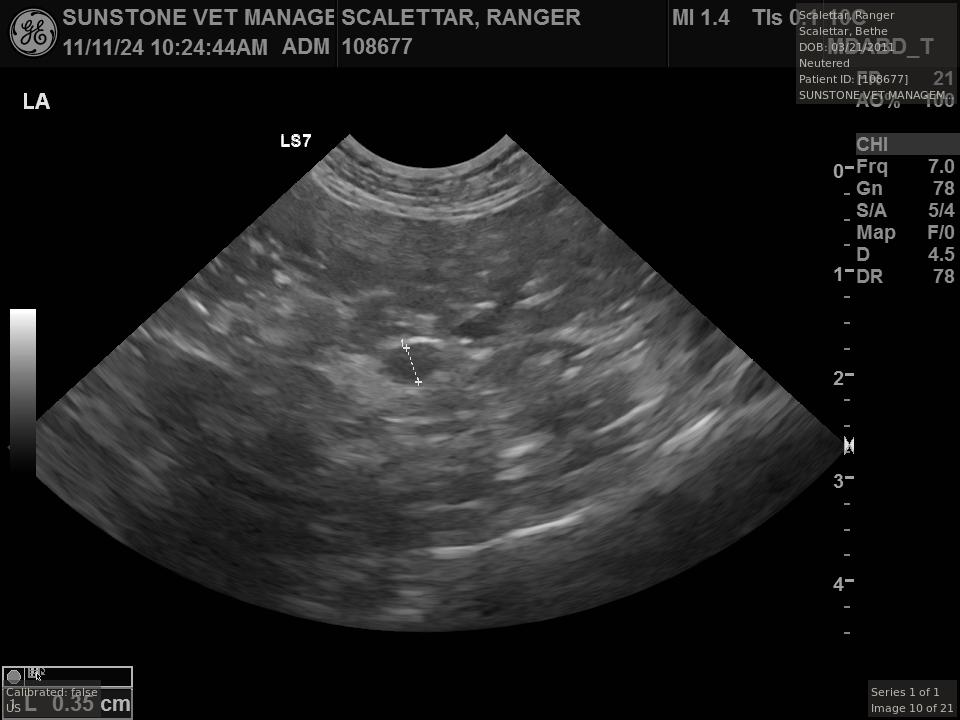

The veterinarian generated a series of images showing different organs and substructures by

changing the position and orientation of the ultrasound transducer. The images were collected

in a defined order, which is repeated from patient to patient, ensuring that nothing is missed. In

Ranger's case, the sonographer collected about twenty images during an examination that

lasted about fifteen minutes.

The sonographer stated that Ranger's ultrasound images were largely normal for an older cat. In particular, they show changes in the kidneys that are commonly noted in geriatric cats and that reflect a risk for the development of chronic kidney disease. However, the images did not show any significant abnormalities in Ranger's stomach, intestines, and associated lymph nodes. Nonetheless, the results did not rule out recurrence of Ranger's small cell lymphoma.